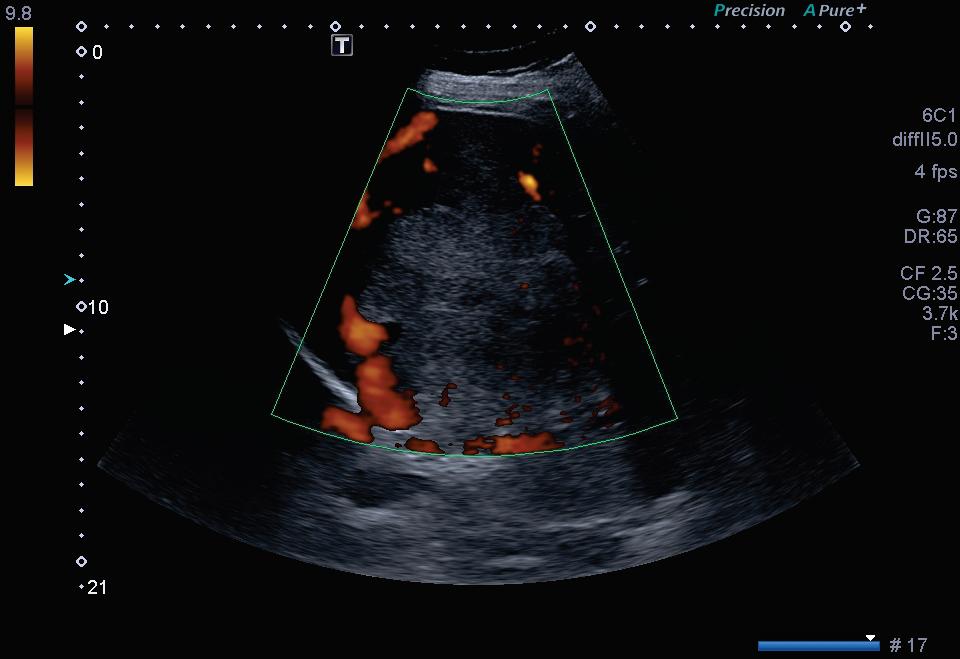

Fig. 2-18. Nódulo na bexiga com vascularização ao Doppler.

Fig. 2-47. “Artefato cintilante” no Doppler posterior ao cálculo.

Fig. 2-69. Nódulo vascularizado na vesícula biliar.

Fig. 4-17. Vascularização usual do linfonodo – padrão hilar (central).

Fig. 4-20. Vascularização aberrante em linfonodo atípico.